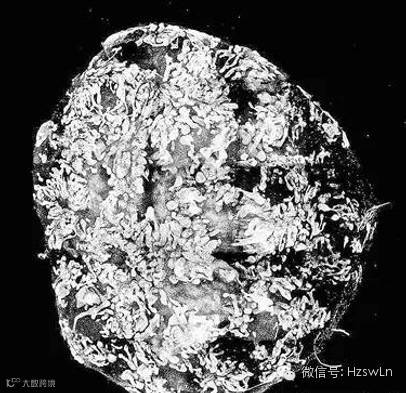

此次,论文作者和他们的研究团队鉴别出了人类多功能干细胞成为收集管还是肾单位祖细胞的信号传导因素及条件。他们在接下来的实验中,用这些新发现培育出了类似肾的结构(类器官),这个结构中肾单位通过收集管的网络相连接,而且还有连接组织和血管祖细胞,后两者在人类胚胎中会包裹着肾单位。在这些肾脏类器官中,表达基因和人类胚胎头三个月肾脏表达的基因极其相似,而且这些类器官在接触到已知的肾毒素时,也会表现出损伤。